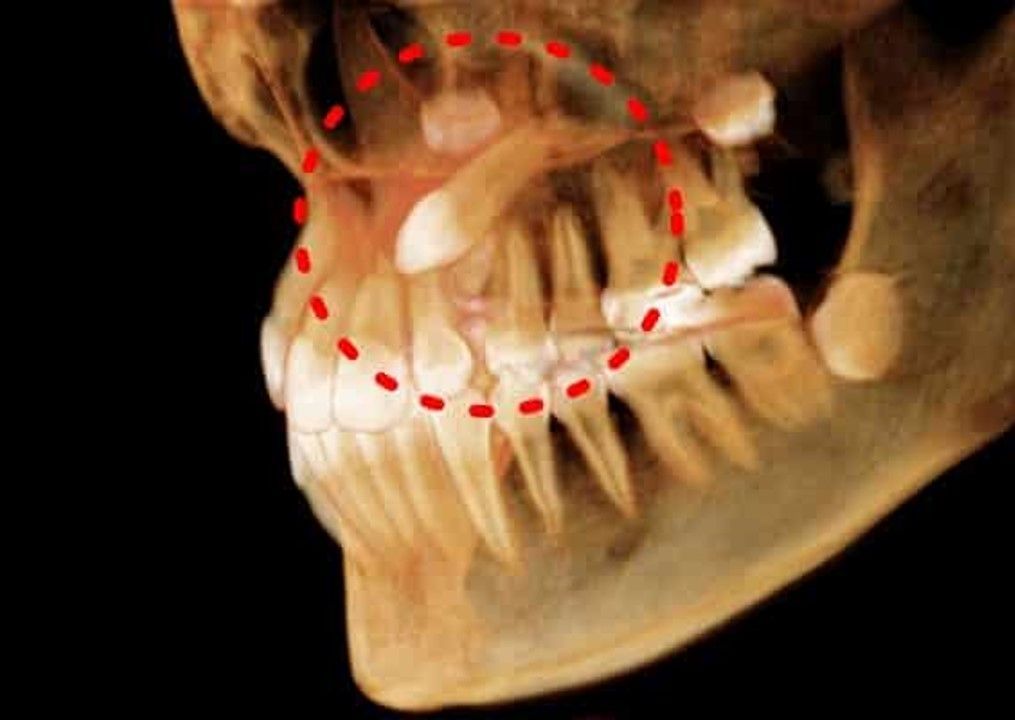

Caninos retenidos

Los caninos superiores, también conocidos como colmillos, en ocasiones suelen quedar retenidos en la encía y no erupcionan en su posición original. Esto es ocasionado por, entre otras cosas, falta de espacio en la mandíbula, otros dientes que estén en su camino o una malposición del diente.

Mediante técnicas de tracción de canino y tracción ortodóntica se puede corregir la posición de los caninos superiores.